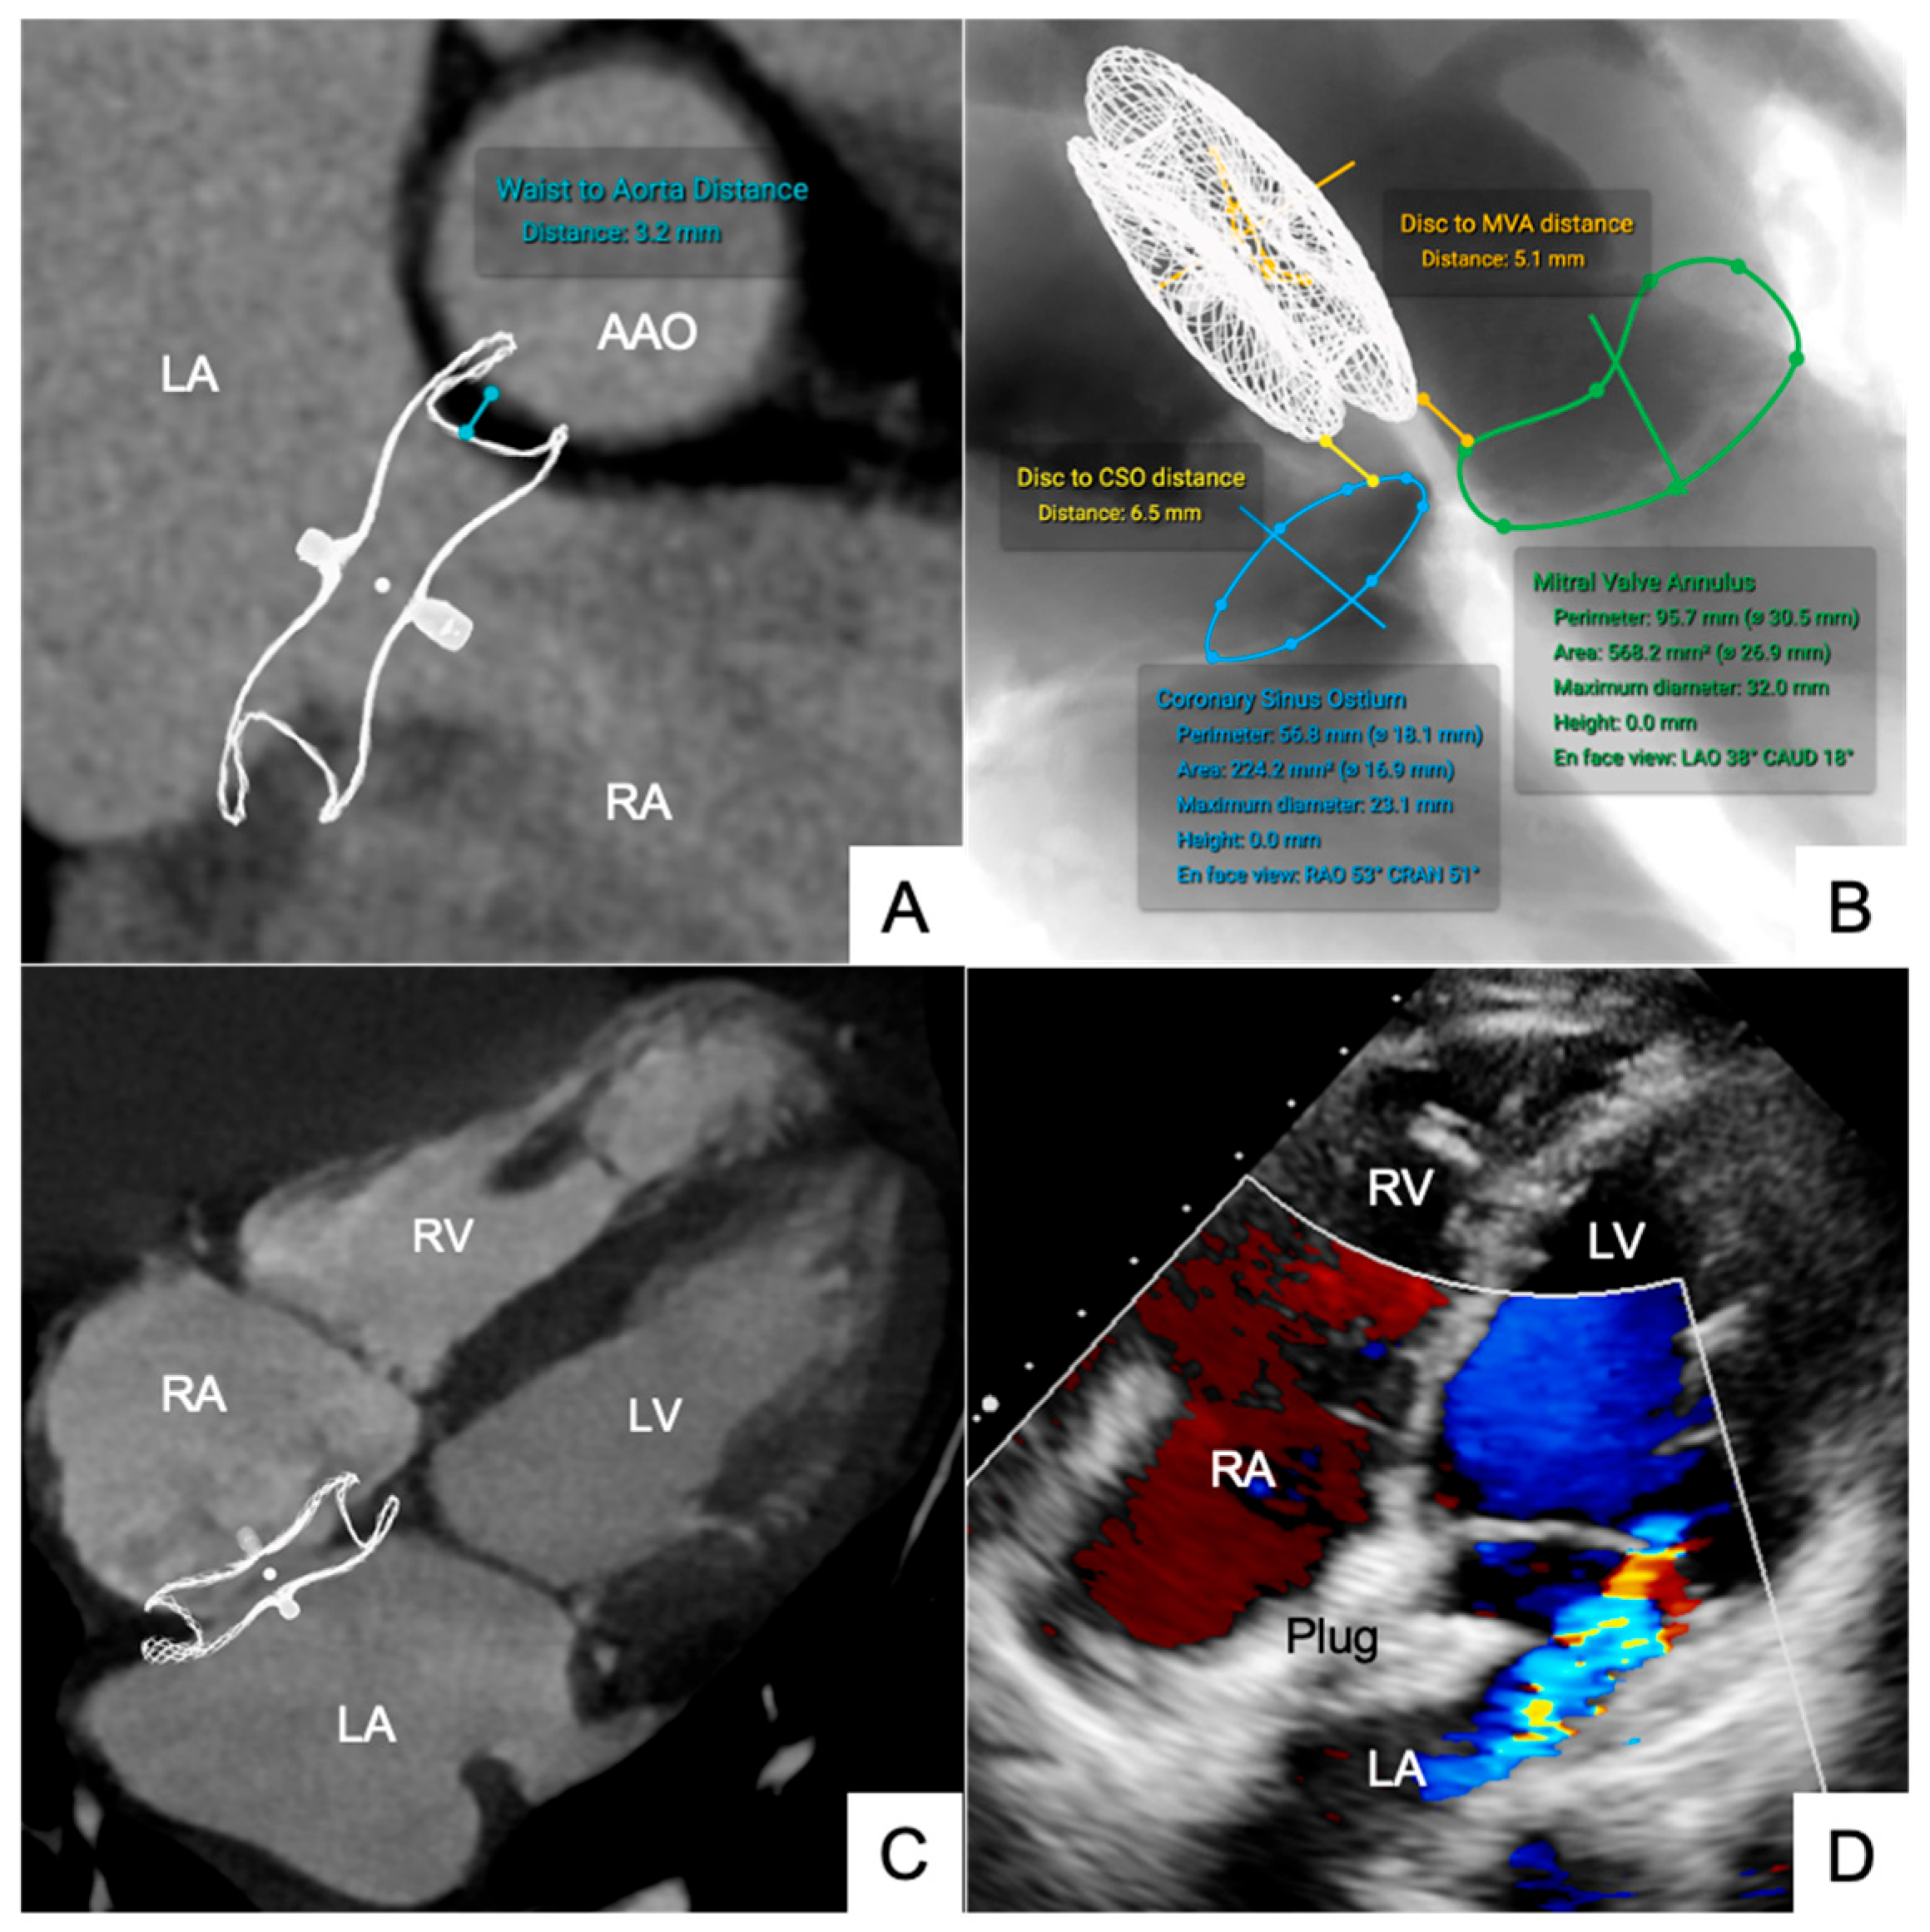

| Waist to AAO | 5.48 ± 2.25 | 6.65 ± 2.30 | 3.12 ± 0.70 | 0.95 | 0.23 | −0.11 to +0.56 | |

| ASD Occluder (n = 6) | Disc to MVA | 9.48 ± 2.20 | 10.70 ± 2.32 | 3.15 ± 0.68 | 0.95 | 0.22 | −0.10 to +0.54 |

| Disc to CSO | 7.28 ± 2.82 | 9.05 ± 3.04 | 5.10 ± 1.16 | 0.96 | 0.21 | −0.12 to +0.50 | |

| LAA Occluder (n = 6) | Disc to MVA | 6.10 ± 2.20 | 6.74 ± 2.30 | 3.88 ± 0.76 | 0.93 | 0.24 | −0.11 to +0.59 |

| Disc to LSPV | 3.82 ± 1.70 | 4.25 ± 2.20 | 2.60 ± 1.05 | 0.91 | 0.22 | −0.10 to +0.55 | |

| Disc to LZP | 6.78 ± 2.05 | 7.20 ± 2.54 | 4.56 ± 1.64 | 0.92 | 0.21 | −0.12 to +0.56 | |